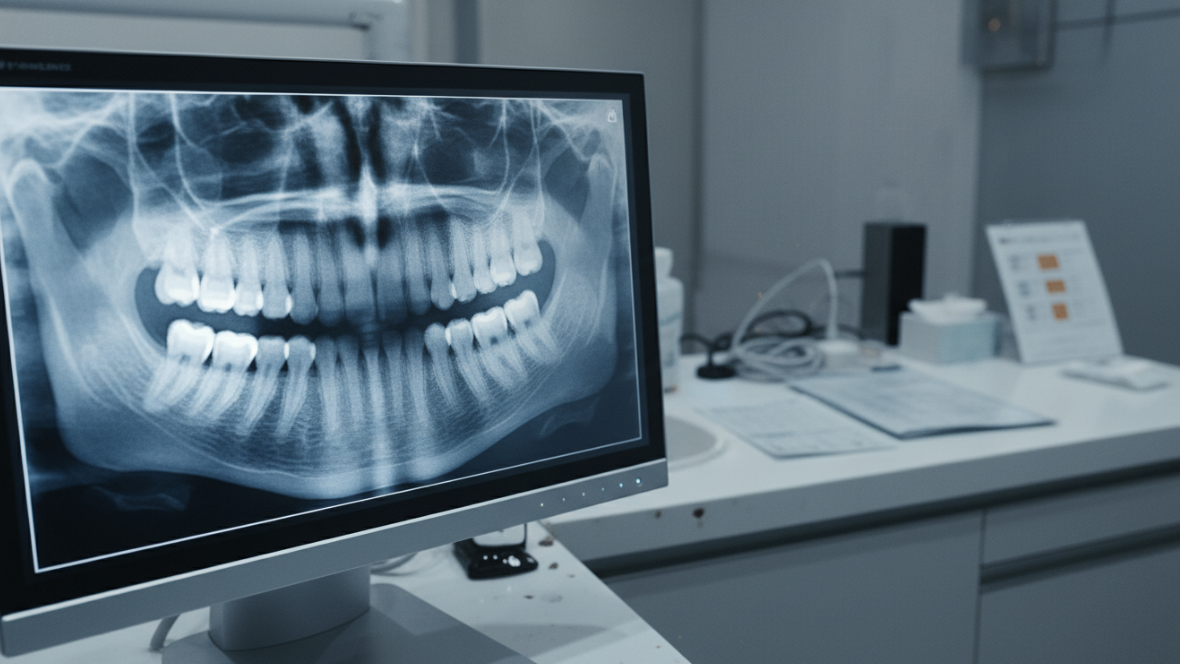

レントゲン検査(エックス線検査)

歯周病がさらに進行すると、歯を支えている骨(歯槽骨)が溶けてきます。

この骨の状態は、歯ぐきの下に隠れているため目で見ることができません。そこで必要になるのがレントゲン検査です。

レントゲン検査では、歯槽骨が溶けてなくなった範囲や程度をかなり正確に知ることができます。骨の吸収度合いを評価することで、歯周病の進行具合を客観的に判断し、今後の治療方針を決定する重要な情報となります。

「放射線被曝が心配」という声もよく聞かれますが、歯科のレントゲン撮影による被曝量は、日常生活で自然界から浴びる1年分の自然放射線の数十から数百分の1程度とされています。安全性は十分に確保されていますので、ご安心ください。